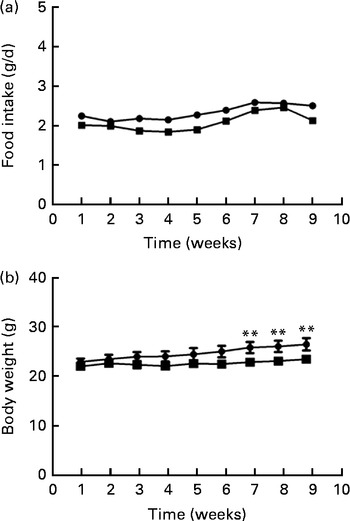

Food intake levels were not different between the two groups at either the beginning (2·22 (sd 0·29) g) or the end (2·23 (sd 0·28) g) of the study (Fig. 1(a)). Body weights differed between the two groups during the last 3 weeks of the study; the body weight of mice fed the FO diet was significantly lower than that of the HFD-fed mice after 8 weeks of intervention (P< 0·01; Fig. 1(b)).

Fig. 1 Food intake (a) and body weight (b) of apoE− / − mice fed a high-fat diet ![]() or a high-fat diet enriched with 10 % fish oil

or a high-fat diet enriched with 10 % fish oil ![]() for 8 weeks. Values are means (n 12), with standard deviations represented by vertical bars. ** Mean value was significantly different from that of the high-fat diet group (P< 0·01).

for 8 weeks. Values are means (n 12), with standard deviations represented by vertical bars. ** Mean value was significantly different from that of the high-fat diet group (P< 0·01).